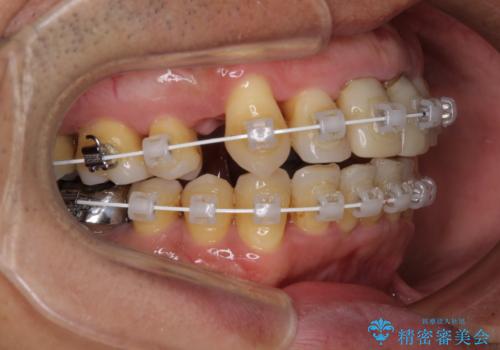

- 矯正装置

- 審美装置

- 2年6ヶ月

- 治療回数

上顎前歯の突出感と右上の八重歯を気にされていたので、上顎左右の第一小臼歯2本を抜歯し、ワイヤー装置にて矯正治療を行うこととしました。